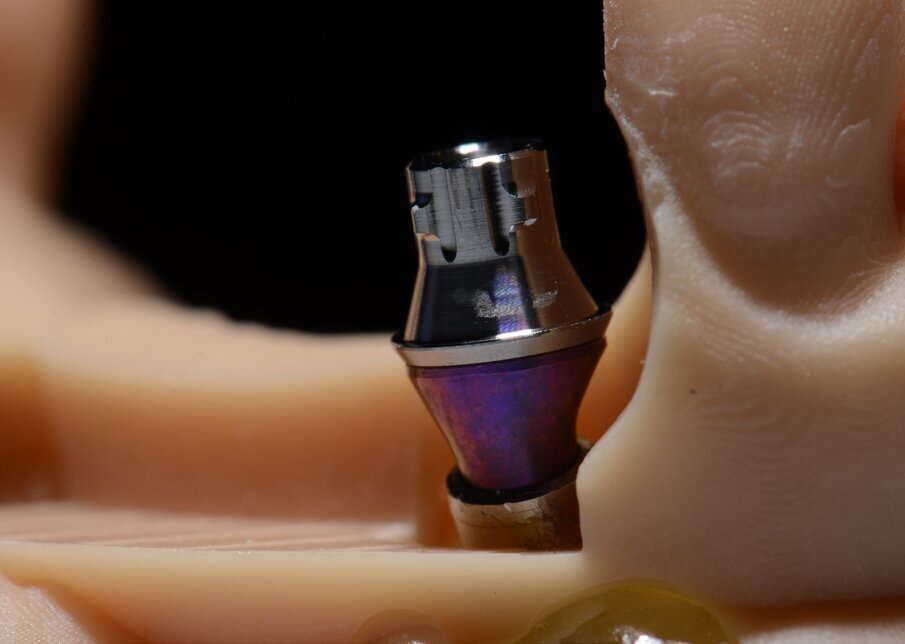

Le fasi successive sono tecniche, uniamo la componente secondaria angolata a 17° programmata agli analoghi degli impianti (Figg. 46-49), su di essa avviteremo il moncone SRA (Figg. 50, 51). Alloggeremo il provvisorio sul modello (Fig. 52) e le alette di riposizionamento ci consentiranno di essere precisi. Unire il provvisorio alle componenti secondarie sarà a questo punto molto semplice con resina fotopolimerizzabile (Fig. 53). In poco più di un’ora abbiamo funzionalizzato il provvisorio (Figg. 54-57). Il montaggio del provvisorio avverrà collegando prima le componenti secondarie angolate agli impianti (Figg. 58, 59) e poi il provvisorio stesso (Figg. 60-70).

Fig. 50 - SRA e variobase.

Fig. 51 - SRA e variobase.

Fig. 56 - Particolari e precisione

Fig. 57 - Particolari e precisione.